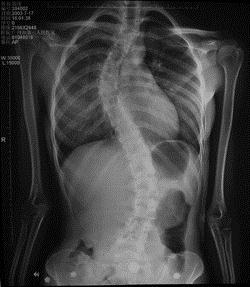

病历摘要: 患者××,女,17岁,发现剃刀背畸形3个月。查体:脊柱胸段向右侧凸,腰段向左侧凸,右胸廓呈剃刀背畸形,双下肢未见明显异常。特发性脊柱侧...

问题 病历摘要: 患者××,女,17岁,发现剃刀背畸形3个月。查体:脊柱胸段向右侧凸,腰段向左侧凸,右胸廓呈剃刀背畸形,双下肢未见明显异常。 特发性脊柱侧弯的Moe分型:

选项 A、胸椎双弧度型 B、单一胸腰椎主弧型 C、单一腰椎主弧型 D、单一胸椎主弧型 E、胸腰椎双弧型 F、胸腰及胸椎双弧度型 G、单一上胸椎主弧型 H、胸椎主弧和腰椎次弧型